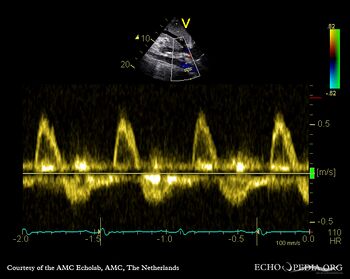

E00808.jpg

Pulsed-wave Doppler signal of flow in abdominal aorta: holodiastolic flow reversal